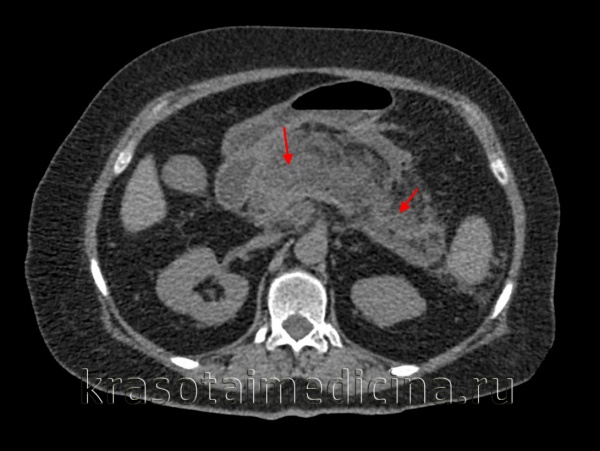

Экспериментально установлено, что включение ремаксола в терапию не только предупреждало прогрессирование острого панкреатита, но и способствовало сравнительно быстрому купированию воспалительных явлений в поджелудочной железе (рис. 2), Рисунок 2. Макроскопическая картина поджелудочной железы с прилежащими к ней тканями на 3-и сутки развития острого панкреатита на фоне применения ремаксола. что сопровождалось снижением активности α-амилазы на 19,7-48,43% (р <0,05) относительно контроля. Одним из характерных признаков благотворного действия препарата явилось уменьшение случаев трансформации морфологических поражений органа (тотальный панкреонекроз отмечен у 1 животного). Безусловно, одним из факторов положительного влияния препарата была быстрая и эффективная коррекция функциональной активности печени и кишечника. Так, на фоне применения препарата активность АСТ и АЛТ незначительно возрастала относительно нормы, но была достоверно ниже контроля на 12,9-11,4 и 14,2-16,0% (р<0,05) соответственно; содержание билирубина и креатинина уменьшалось по сравнению с контролем на 8,3-16,2 и 9,6-34,1% (р<0,05) соответственно. Проницаемость сосудов микроциркуляторного русла кишечника для воды и белка была ниже, чем в контрольной группе (рис. 3); Рисунок 3. Показатели транскапиллярного обмена в ткани кишечника при остром панкреатите на фоне применения ремаксола. Здесь и на рис. 4: * - достоверность различия показателей по отношению к контролю при p<0,05; к - данные контрольной группы исследований; о - данные опытной группы исследований); КФ - капиллярный фильтрат, ПБ - потеря белка. коэффициент диффузии кислорода возрастал относительно контрольных данных на 53,9-57,1% (p<0,05); окислительно-восстановительный потенциал превосходил контроль на 22,93-29,68% (p<0,05).